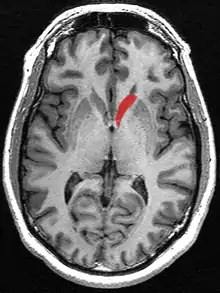

![]() Caudate nucleus (in red) shown within the brain | |

The caudate nuclei are located near the center of the brain, sitting astride the thalamus. There is a caudate nucleus within each hemisphere of the brain. Individually, they resemble a C-shape structure with a wider "head" (caput in Latin) at the front, tapering to a "body" (corpus) and a "tail" (cauda). Sometimes a part of the caudate nucleus is referred to as the "knee" (genu).[7] The caudate head receives its blood supply from the lenticulostriate artery while the tail of the caudate receives its blood supply from the anterior choroidal artery.[8]